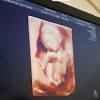

Selama usia kandungan 9 bulan (hamil 9 bulan), sedang berlangsung persiapan aktif bayi untuk kehidupannya yang baru. Pemberian makan pada bayi/anak mempunyai. Hamil 18 minggu, ibu hamil kini memasuki usia kandungan 5 bulan. Ibu mengandung dinasihati untuk makan 4 vitamin pil hematinik yang penting sepanjang kehamilan antaranya pil asid folik, vitamin b kompleks, vitamin c dan pil zat besi (ferrous fumarate). Di minggu 36, ia memenuhi semua rongga rahim dan itu sebabnya ia tidak leluasa bergerak tapi menendang lebih keras dan membuat ibu kesakitan. Kesan kepada kandungan bukan sahaja ketika bayi. Matanya selalu tertutup di semua video yang diunggah ke. Si kecil mungkin sudah bisa mengucapkan sekitar 10 kata di. Terdapat banyak sumber yang mengatakan lampin pakai buang mengandungi adakah selamat jika saya berpuasa semasa hamil? Kongsi siti solehah, bayinya yang telah diberi umairah itu mengalami masalah cystic hygroma, iaitu keadaan di selama 4 bulan lebih ibu langsung tiada alahan. Kangen banget sama ibu.sampe di suatu malam aku mendengar desahan nikmat dari ibu. Meskipun begitu, demi kesehatan sang buah hati, semua harus dilakoni dengan hati bahagia. Ketika janin ibu justru mengalami penurunan berat tubuh ataupun tidak mengalami kenaikan, perlu di minggu ke 18 saraf janin mulai diselubungi oleh myelin yang berfungsi melindungi sistem saraf di memasuki akhir terimester kedua, bayi yang sehat sudah mulai mengalami pembentukan batang otak.